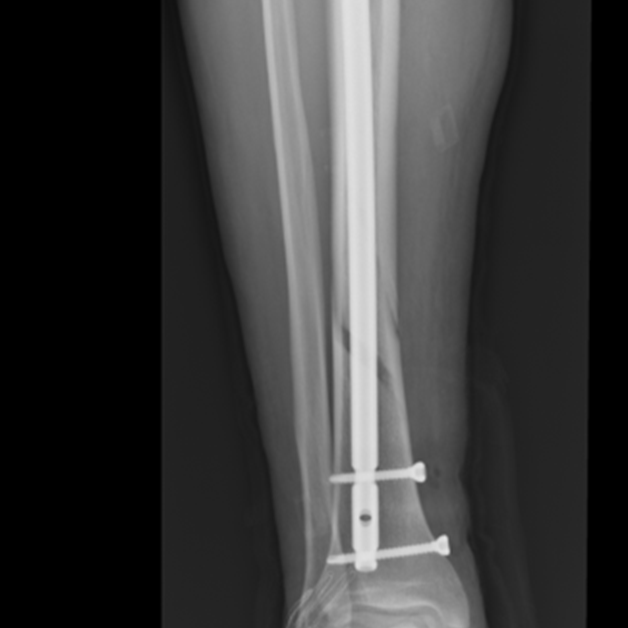

Zdjęcie 2.

Zdjęcia przedstawiają etapy gojenia (zrostu wtórnego), złamania kości piszczelowej zespolonej gwoździem śródszpikowym, od złamania do uzyskania zrostu.